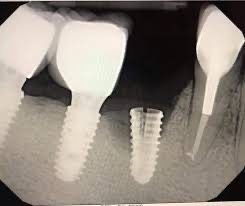

3️⃣ 植牙最怕的就是「過度咬力」

磨牙者的植牙承受壓力比一般人高很多:

• 螺絲鬆動

• 假牙破裂

• 植體周圍炎惡化

• 甚至植體本體鬆脫

都是臨床上很常見的問題。

戴咬合板能把過度咬力平均分散,大幅延長植牙使用年限。